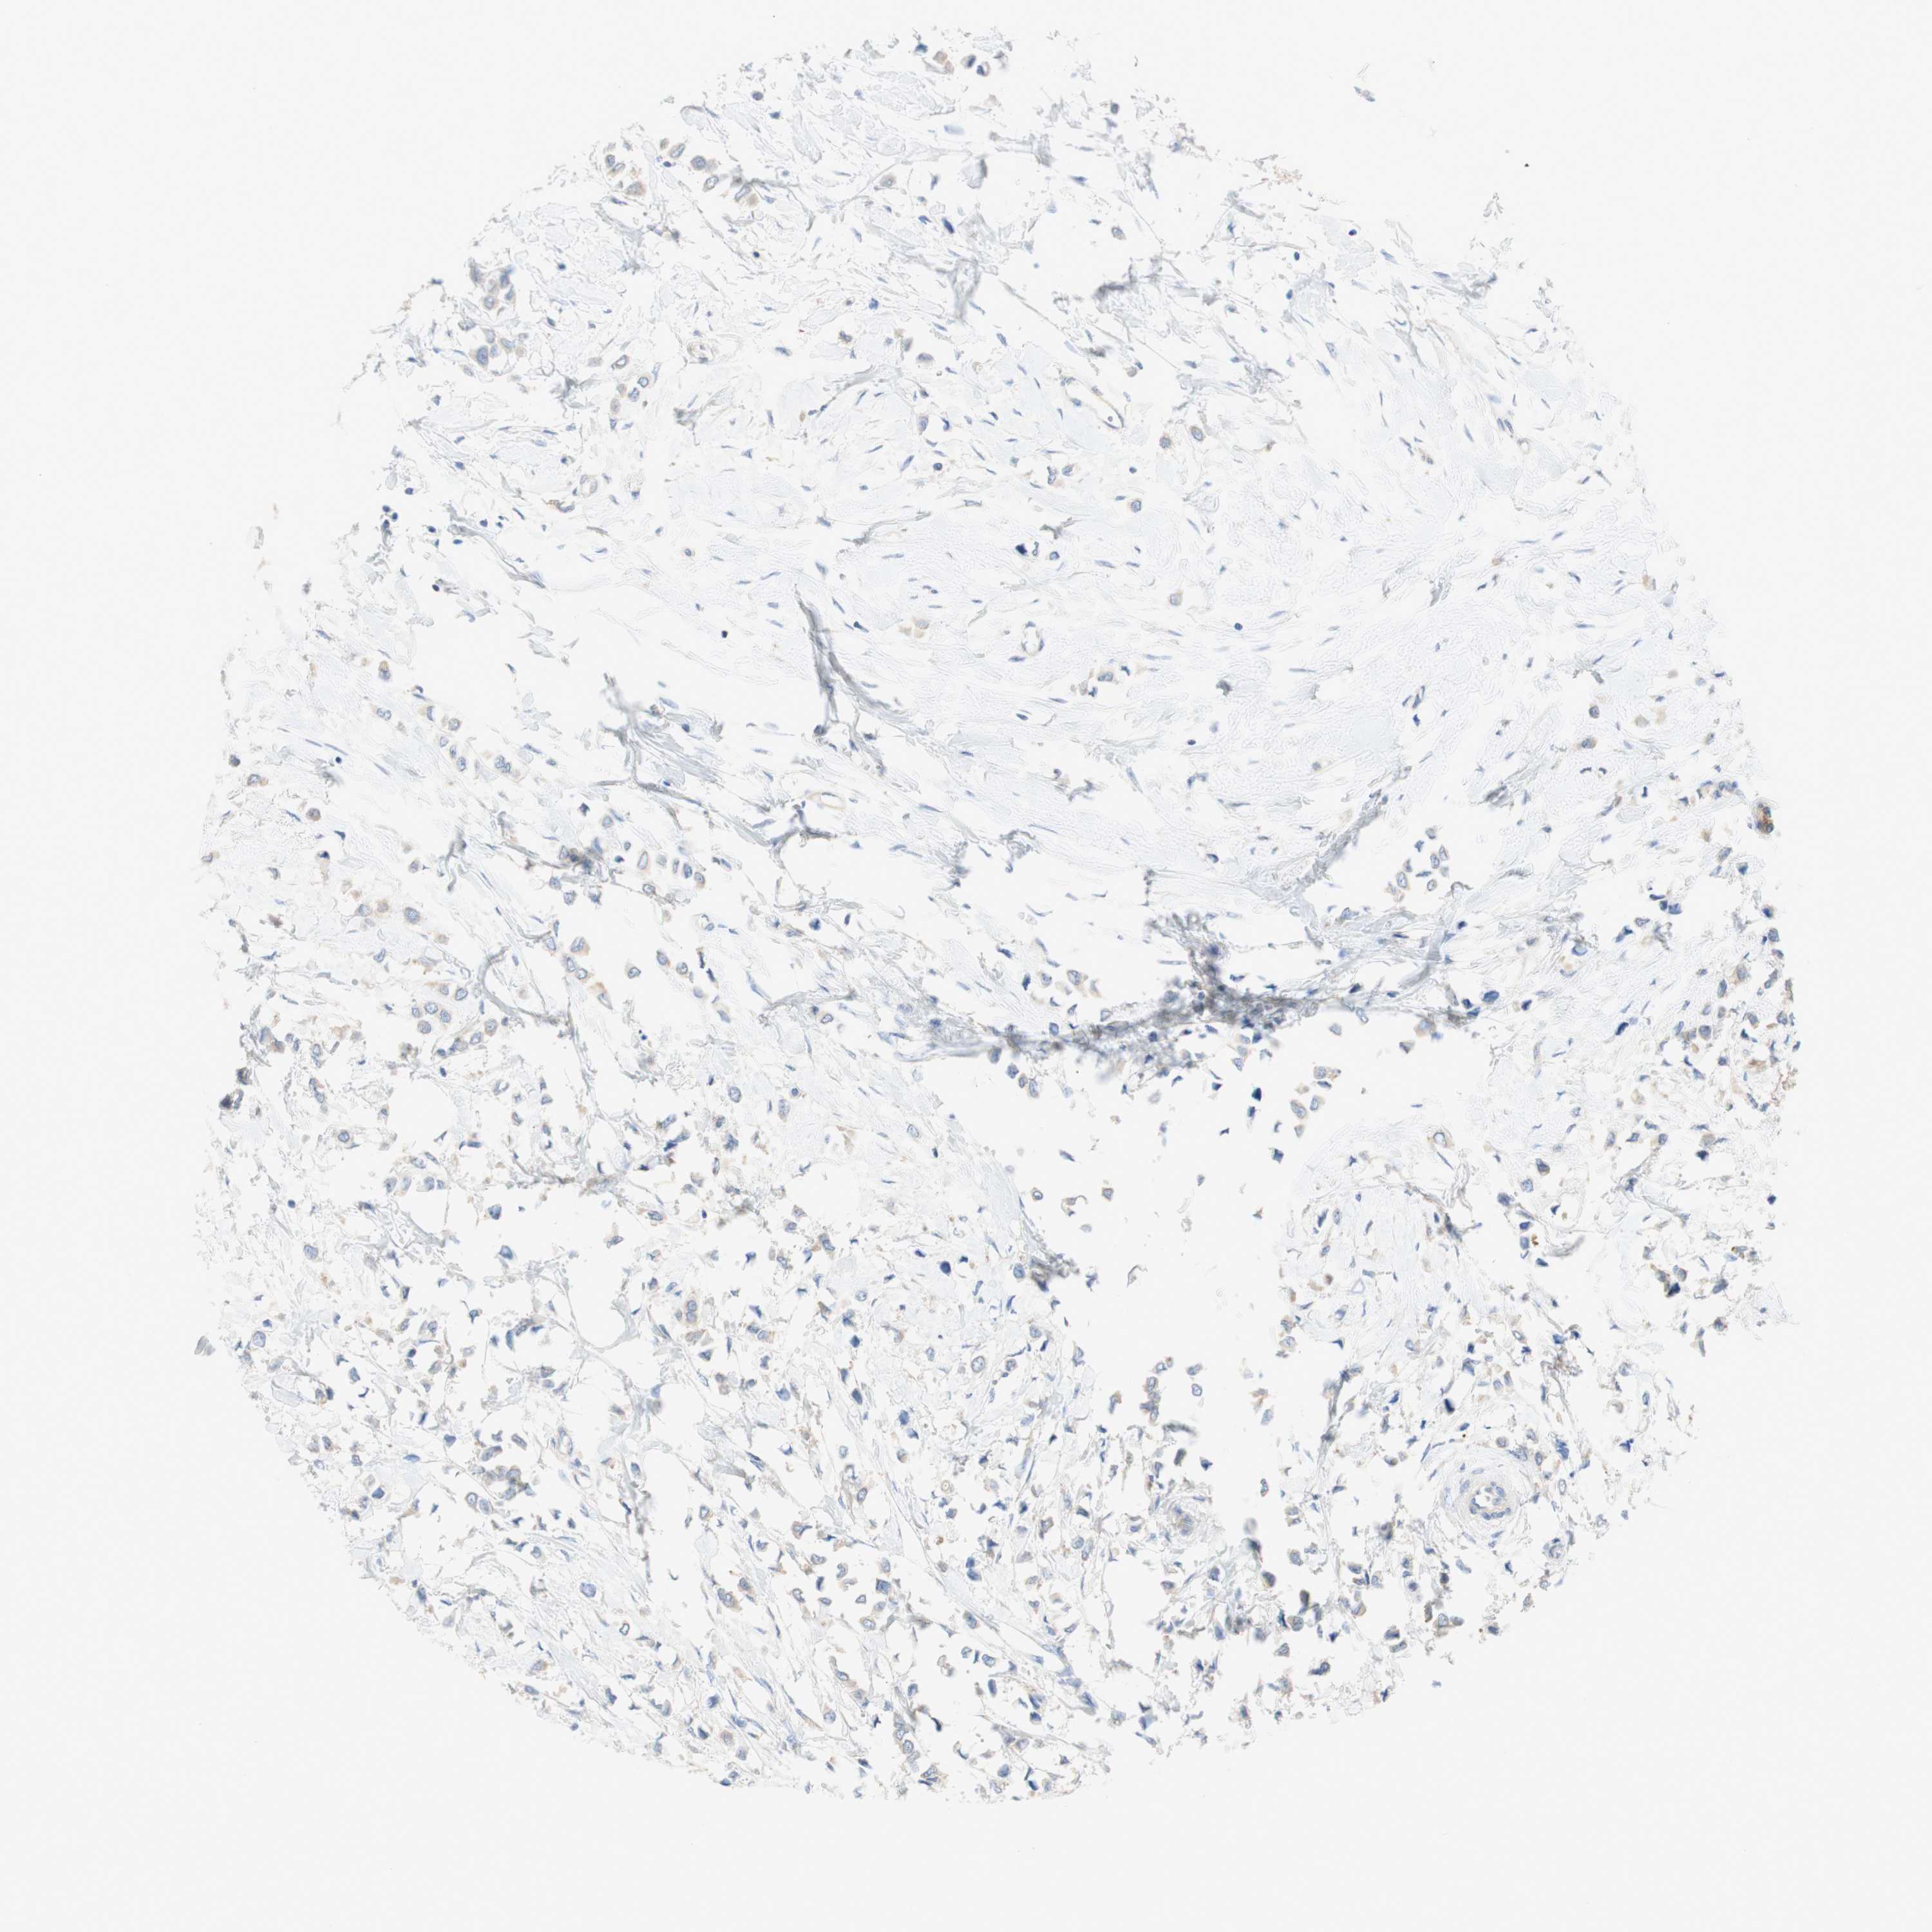

BRCA TCGA BRCA VALIDATION PROTEIN EXPRESSION